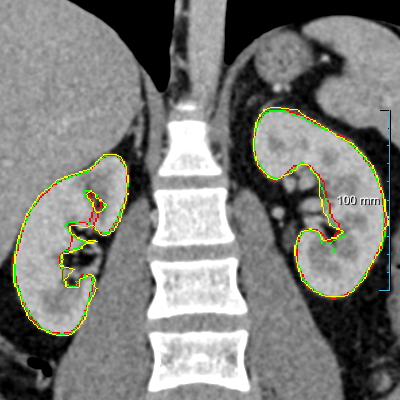

Refer to caption

(a) Patients without kidney abnormalities.

(b) Patients with kidney abnormalities.

Figure 3: Four examples of CT scans from the training set (dataset A) showing coronal sections with annotations in format 2 (see Figure 2(c)) where yellow and red overlays represent annotations of the parenchyma and kidney abnormalities, respectively. Note that all the patients have anomalies in the body (green arrows in the body), and both cases of (b) have only one kidney and contain kidney abnormalities. All the slices have a window center of 60 HU and a window width of 360 HU.

Samples of CT scans from patients included in this study can be seen in Figure 3. While Figure 3(a) depicts patients without kidney abnormalities, it highlights the presence of abnormalities in other parts of the body, such as liver tumors. Figure 3(b) shows patients with kidney abnormalities, as well as other abnormalities in the body, such as nephrectomy and collapsed lung.